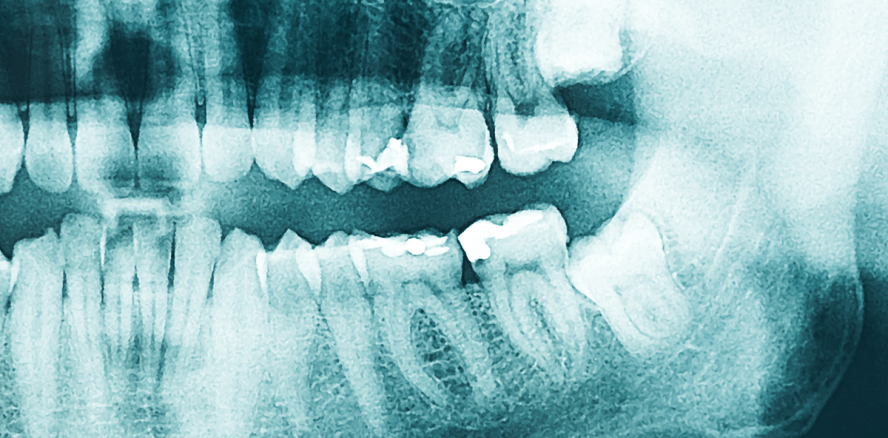

Foto: © radub85 – Fotolia.com

Ein leicht entzündeter Weisheitszahn kostete einem jungen Mann jetzt fast das Leben. Über den Zahn gelangten Bakterien in den Blutkreislauf, die schließlich an seinem Herzen halt machten und dieses langsam zerfraßen. Nur eine siebenstündige OP, bei der ihm eine neue Herzklappe eingesetzt wurde, rettete dem Engländer das Leben.

Eine Woche später und Daniel Murtagh wäre wahrscheinlich an den Folgen seiner leichten Zahnentzündung gestorben, so sehr wurde sein Körper bereits in Mitleidenschaft gezogen. Nachdem er mehrere Monate über Schmerzen und Erschöpfung klagte und zudem noch stark an Gewicht verlor, vermuteten die Ärzte, der 29-Jährige sei an HIV erkrankt. Ein durchgeführter Test kam jedoch negativ zurück. Dieser offenbarte allerdings, dass Daniel eine Herzinnenhautentzündung hat. Da der Grund für die Infektion erst spät entdeckt wurde, konnten sich die Bakterien im Körper ausbreiten und so das Herz des Engländers schwächen. Erst nach acht Monaten konnten die Ärzte den Ort der Infektion ausfindig machen: ein kleiner schwarzer Punkt an einem seiner Weisheitszähne. Sofort wurde dieser entfernt und in einer siebenstündigen Operation bekam Daniel eine neue Herzklappe eingesetzt. Zu diesem Zeitpunkt pumpte sein Herz nur noch 30 Prozent Blut durch den Körper. Sein Gehirn wurde nicht ausreichend mit Sauerstoff versorgt, was auch die permanente Erschöpfung erklärte.